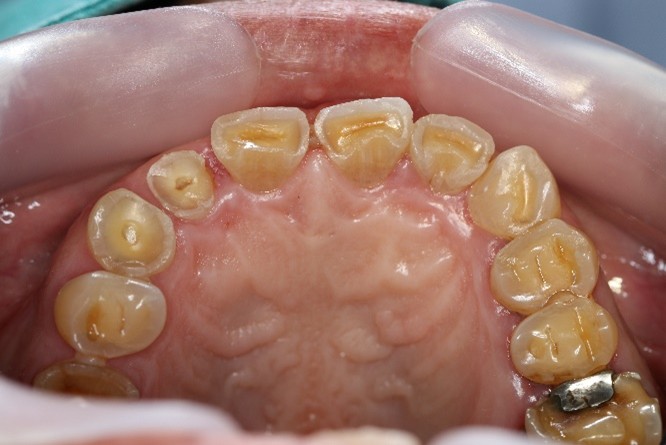

If your teeth appear shorter, flatter, or have worn-down occlusal cusps, you may already be experiencing occlusal trauma. Other warning signs include chipping or fracturing of teeth and restorative work such as fillings, veneers, or crowns. These are not merely cosmetic issues—they indicate that applied forces generated between the upper and lower dentition exceed the tolerance of tooth tissues. When these excessive forces surpass the enamel’s ability to withstand pressure, microfractures, chipping, and accelerated wear occur.

Occlusal wear is a significant clinical phenomenon that affects many individuals, often without them even realizing it. It refers to the gradual loss of tooth structure caused by mechanical forces during biting and chewing. While wear is a normal part of the aging process, it becomes problematic when accelerated by factors such as traumatic occlusal forces. One of the leading causes of these forces is an unstable stomatognathic system — the complex network of muscles, joints, and teeth that work together to facilitate chewing, swallowing, and speaking.

- Untreated occlusal wear progression: It creates a snowball effect—deterioration progresses more rapidly over time, leading to increasingly harmful consequences at a much faster rate. As occlusal wear progresses, the deterioration becomes continuous and increasingly difficult to control. In the more advanced stages, the process accelerates, leading to faster breakdown of tooth structure and greater functional instability.